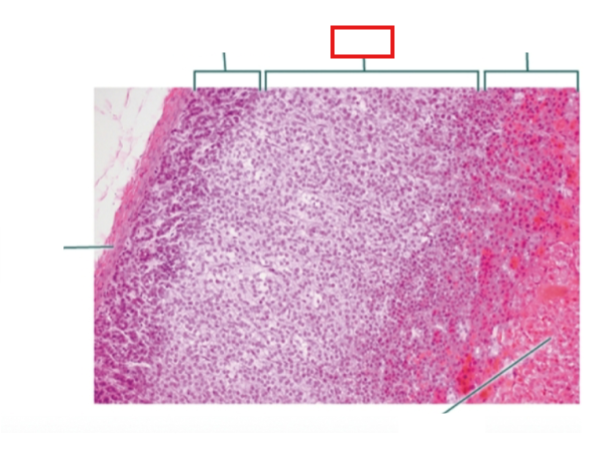

What structure is highlighted?

zona glomerulosa

What structure is highlighted?

zona fasciculata

What structure is highlighted?

zona reticularis

What structure is highlighted?

Capsule

What structure is highlighted?

medulla

What structure is highlighted?

capsule

What structure is highlighted?

zona glomerulosa

What structure is highlighted?

zona fasciculata

What structure is highlighted?

zona reticularis

What structure is highlighted?

adrenal medulla

What tissue is shown?

adrenal gland